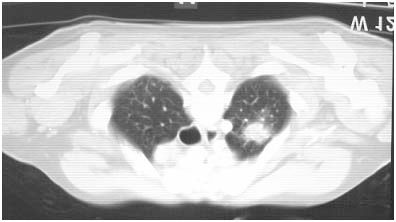

Figure 2- Left upper lobe nodule 2.2cm by 1.9cm

Differential diagnoses considered at this point include: TB, primary lung or metastatic neoplasm, granulomatous lung disease (broad differential), aspergilloma, septic emboli, and other pathogens. Thoracoscopic biopsy for definitive diagnosis is shown (Figures 3,4).